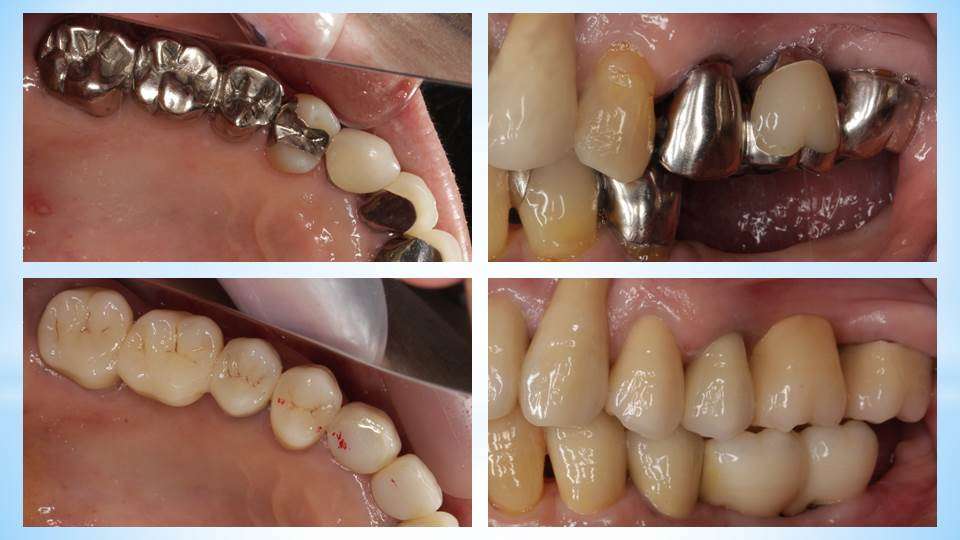

流山のグランツ歯科クリニックでは「銀歯ばっかりのお口の中」を白い歯で治療をします。

流山のグランツ歯科クリニックでは「色んな種類のセラミックス」で治療が受けられます。